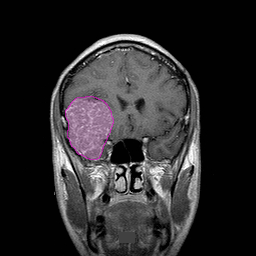

Διάγνωση Απαραίτητα είναι: Η λεπτομερής λήψη ιστορικού και η κλινική εξέταση, Η μαγνητική τομογραφία του εγκεφάλου με σκιαγραφικό, Σε ορισμένες περιπτώσεις: Η μαγνητική αγγειογραφία ή/και φλεβογραφία του εγκεφάλου, Η μαγνητική φασματοσκοπία, Η μαγνητική τομογραφία του εγκεφάλου με σκιαγραφικό για νευροπλοήγηση, Σε περίπτωση εξεργασίας/εξεργασιών με υποψία μεταστατικής προέλευσης επιπλέον ογκολογικός έλεγχος (απεικονίσεις άλλων οργάνων, καρκινικοί δείκτες κα) |

Θεραπεία Η θεραπεία των πρωτοπαθών όγκων εγκεφάλου είναι κατά κανόνα χειρουργική, και αυτό γιατί αποτελεί τον πλέον άμεσο και αποτελεσματικό τρόπο να αποσυμπιεστεί ο εγκεφαλικός ιστός ή τα κρανιακά νεύρα τα οποία πιέζονται. Επίσης κατά την διάρκεια της επέμβασης λαμβάνονται βιοψίες από την εξεργασία προκειμένου να ταυτοποιηθεί ιστολογικά και να αντληθούν πληροφορίες για την πρόγνωση και την ανάγκη περαιτέρω θεραπείας (ακτινοθεραπεία ή/και χημειοθεραπεία). Η έκταση της επέμβασης (βιοψία έως ολική εξαίρεση) ορίζεται από πολλούς παράγοντες, όπως το μέγεθος, η θέση και η σχέση της εξεργασίας με ζωτικά ή ευγενή κέντρα του εγκεφάλου. Οι μεταστατικές βλάβες του εγκεφάλου είναι όχι σπάνια πολλαπλές. Σε αυτή την περίπτωση αξιολογείται η ανάγκη βιοψίας (στις περιπτώσεις που η προέλευση της βλάβης δεν είναι τελείως προφανής). Συχνά αντιμετωπίζονται με συνδυασμό ακτινοχειρουργικής/ακτινοθεραπείας και χημειοθεραπείας. Χειρουργική αντιμετώπιση μπορεί να προταθεί σε περιπτώσεις μονήρους μετάστασης ή, στην περίπτωση πολλαπλών μεταστάσεων, μεγάλης μετάστασης που προκαλεί συμπτώματα. |